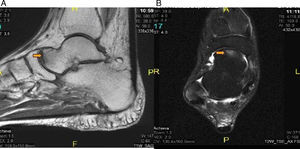

(A) Bone scintigraphy using 99mTc, which reveals a severe lesion in the naviculocuneiform region of right tarsus. (B) Sagittal magnetic resonance imaging in short tau inversion recovery (STIR) sequences with an increased signal intensity. More evident at the intermediate cuneiform level and right lateral region.

We present the case of a male HIV-positive patient (diagnosed in 1999), who began antiretroviral therapy with the following regimen. From September 1999 to November of the same year, he took stavudine (d4T) plus didanosine (ddi) and nelfinavir. In November, he changed to zidovudine (AZT) plus lamivudine (3TC) and nevirapine, which he maintains until July 2008, when he began with emtricitabine, plus tenofovir, as well as nevirapine, until the present time. In 2011, he came to the rheumatology clinic with a 2-month history of pain in the dorsum of his right foot, with no previous injury. He underwent bone scintigraphy using Tc-99m, which revealed a severe trauma in the naviculocuneiform region of the right tarsus and a focal lesion of the third metatarsal bone of the right foot, suggestive of a stress fracture (last densitometry, T-score in femur: −2.3 standard deviations [SD]; T-score in spine: −2.4 SD) (Fig. 1A). Magnetic resonance imaging (MRI) showed a clear signal alteration in midfoot, which was manifested as a somewhat lower signal intensity in T1 and an increase in short tau inversion recovery (STIR) sequences, with a discreetly higher signal intensity at the base of the third metatarsal bone. The suggested diagnosis was a stress fracture of right midfoot affecting the naviculocuneiform joint, at the cuboid and third metatarsal bone of the right foot (Fig. 1B). He was treated with nonsteroidal anti-inflammatory drugs (NSAID) and rest. Three months later, the fracture had healed without side effects. In 2012, after an overexertion, the patient presented with mechanical pain in the region of the metatarsus of the left foot. As another stress fracture was suspected, he underwent MRI, which revealed bone edema in the diaphysis of the second metatarsal bone, and in the neighboring soft tissue, consistent with a stress fracture of the second metatarsal bone of the left foot (Fig. 2A and B). He was treated with rest and conservative measures and, the symptoms disappeared in 2 months (plain radiography showed an image of a fracture callus in the diaphysis of the second metatarsal of the left foot (Fig. 2C). On the 30th of January of 2014, the patient returned to the rheumatology clinic, with an increase in the volume of right ankle after another overexertion (a simple walk). Given the possibility of another fracture, he was studied by MRI, which showed a linear image at the level of the talar head, adjacent to the talonavicular joint. He also had a subchondral lesion at the level of the talus (talonavicular joint) with an irregular increase in the talus (Fig. 3A and B).